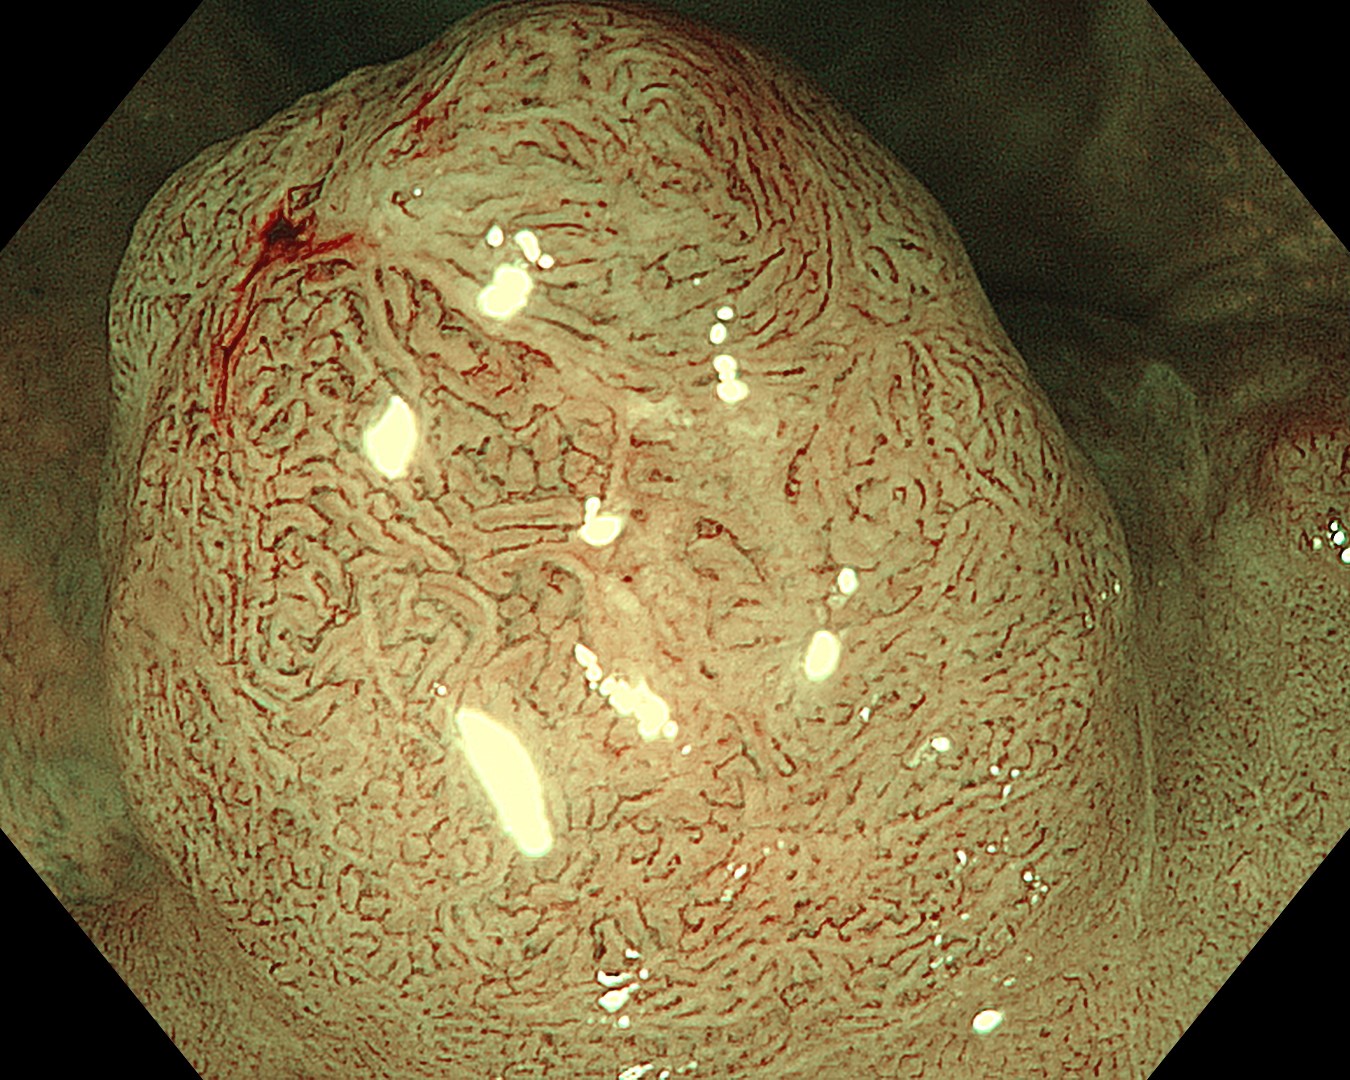

• NBI+TXI観察②(近景)

切替前:NBI強調設定:B8

NBI+TXIレベル:高

図7

平坦隆起部でも、NBI+TXI観察では、血管密度の上昇や分岐異常を伴う領域がより容易に捉えられた。